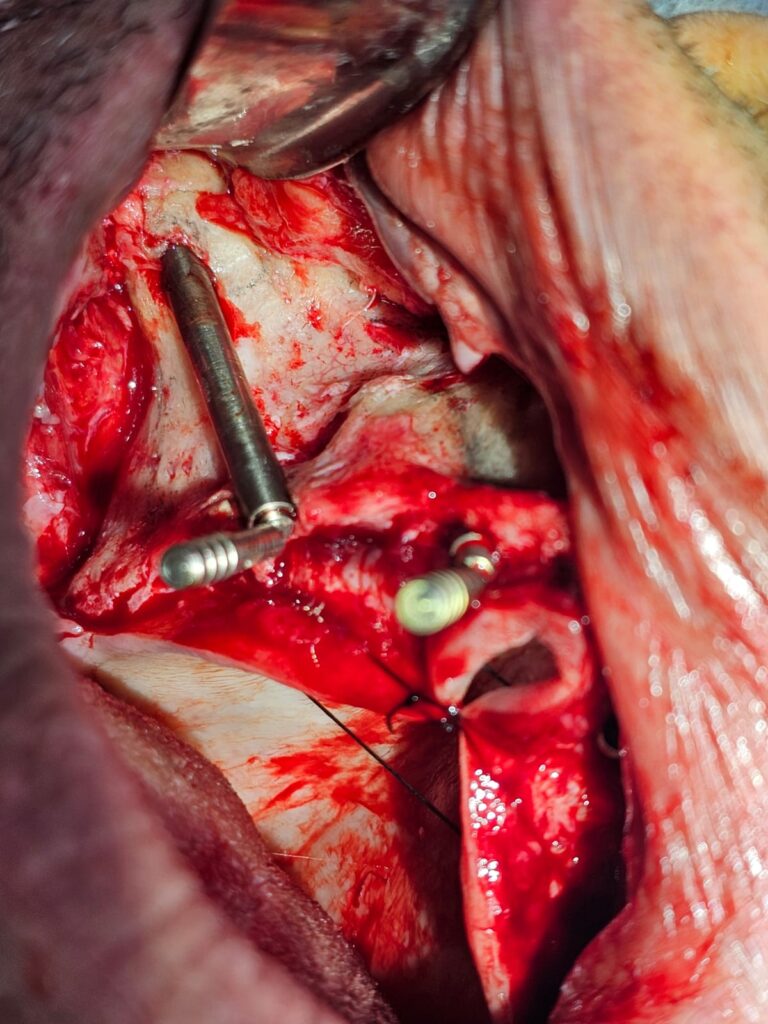

2. Tecniche All-on-4 e All-on-6

3. Grande rialzo del Seno Mascellare

4. Trasposizione dei mentonieri

5. Prelievi ossei e Tecniche Ricostruttive

6. Complicazioni e Gestione degli Insuccessi

CORSO DI IMPLANTOLOGIA ZIGOMATICA

1. Impianti Zigomatici

2. Implantologia Nasale e Pterigoidea